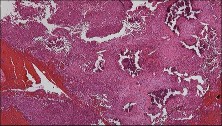

A 15-year-old male presents with chronic knee pain. Radiographs reveal an eccentric, lytic lesion confined to the epiphysis of the proximal tibia. A biopsy is performed.

Histological evaluation demonstrates mononuclear cells with grooved nuclei ('coffee bean' appearance) and areas of pericellular 'chicken-wire' calcification. What is the most likely diagnosis?

Explanation

The diagnosis is Chondroblastoma, a benign but locally aggressive cartilaginous bone tumor that characteristically arises in the epiphysis or apophysis of long bones in skeletally immature or young adult patients. Histological hallmarks include mononuclear chondroblasts with grooved or clefted nuclei ('coffee bean' nuclei), multinucleated osteoclast-like giant cells, and fine lattice-like 'chicken-wire' pericellular calcifications.